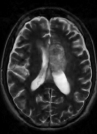

Note that term 2 is sparse if there are no major changes between and , both images have similar grey-level intensities and they are spatially matched. While these conditions meet in many application of dynamic imaging, such as prior image constrained compressed sensing (PICCS) in CT (Chen et al., 2008; Lauzier et al., 2012) and dynamic MRI (Jung et al., 2009; Lustig et al., 2006; Gamper et al., 2008; Yip et al., 2014), in longitudinal MRI none of these requirements are guaranteed. While there are solutions for miss-registration and variable grey level intensities (see Section 4), the temporal similarity in longitudinal MRI is a-priori unknown. Although longitudinal MRI may exhibit temporal similarity (Samsonov et al., 2010), we have to take into account that in many cases the follow-up scan may exhibit substantial changes with respect to the baseline scan. Such cases may occur, for example, if a surgical intervention was applied between the time points or if there is a major progressive or therapy response. Figure 2 shows two representative examples.

Baseline 4 months Baseline 3 months

Hydrocephalus GBM

Therefore, using (2) for image reconstruction under the assumption of substantial similarity between time points might result in improper reconstruction in cases where this assumption does not hold. To avoid this we have to carefully design a sampling and reconstruction mechanism that will be adjusted to match the temporal similarity of the case at hand. To achieve this goal, we extend TCS-MRI using weighted reconstruction and adaptive sampling.